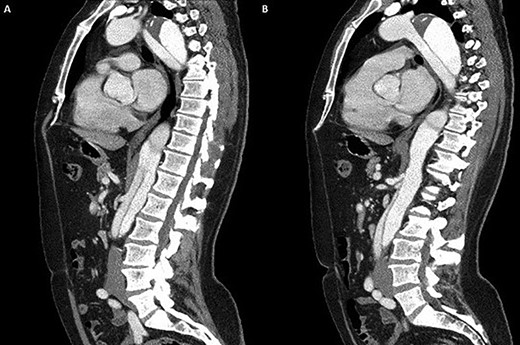

3D reconstruction of the CT scan demonstrating the four-vessel arch configuration with the aberrant left vertebral artery located in the Zone 2 region.

A 52-year-old gentleman presented to our institution with a previous history of TBAD (diagnosed 3 years previously), which was managed conservatively. His comorbidities included hypertension and excision of a left frontal cavernoma with no family history of aortic aneurysm or dissection. Following his initial presentation of chest pain, the patient had remained asymptomatic and stable. Surveillance management was initially instituted and the case discussed at the aortic multidisciplinary meeting. Due to retrograde extension of the TBAD into the distal arch, persistence of the false lumen, increasing descending aortic dimensions (6.0 cm) and an anomalous left vertebral artery originating from the aortic arch, the patient proceeded to aortic arch surgery and antegrade deployment of the stent into the descending aorta with a FET graft (Figs 1, 2). Preoperative coronary angiography and transoesophageal echocardiography revealed no coronary artery disease and a competent trileaflet aortic valve with preserved left ventricular function.

Our case demonstrates the successful use of FET for complicated TBAD as demonstrated previously [10]. The aberrant left vertebral artery originating directly from the aortic arch in the Zone 2 region is the most commonly observed variant, its incidence in a four-vessel epiaortic vessel configuration ranges from 0.68 to 5% [7]. Furthermore, an aberrant left vertebral artery is associated with a higher incidence of arterial dissection ranging from 0.9 to 1.9% [8]. Concerning aortic arch anomalies, the anatomical configuration of an aberrant left vertebral artery in the Zone 2 region pertains to challenging anatomy for TEVAR deployment. However, hybrid TEVAR with stent deployment into the conventional Zone 2 position and cervical transposition of the left vertebral artery to the left common carotid artery has been described [9]. Similarly, hybrid TEVAR with supra-aortic total debranching of the epiaortic vessels and cervical transposition of the left vertebral artery to the left common carotid artery with stent deployment into the Zone 2 position has also been reported [10]. Although not previously described, the surgical technique of reanastomosing the aberrant left vertebral artery to a Dacron graft and subsequent anastomosis to the perfusion limb of the Thoraflex graft mitigates the need for any concomitant cervical anastomosis of the aberrant left vertebral artery and favourably addresses this rare anatomical variation.